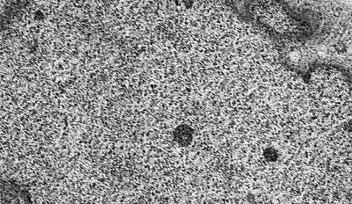

Next, researchers from OIST’s former Brain Mechanisms for Behavior Unit measured the function of the neurons within the hippocampus of the mice without the Tob gene. They found that excitation was increased, while inhibition was decreased, suggesting that the overall balance was impacted, which would impact the behavior of the mice.